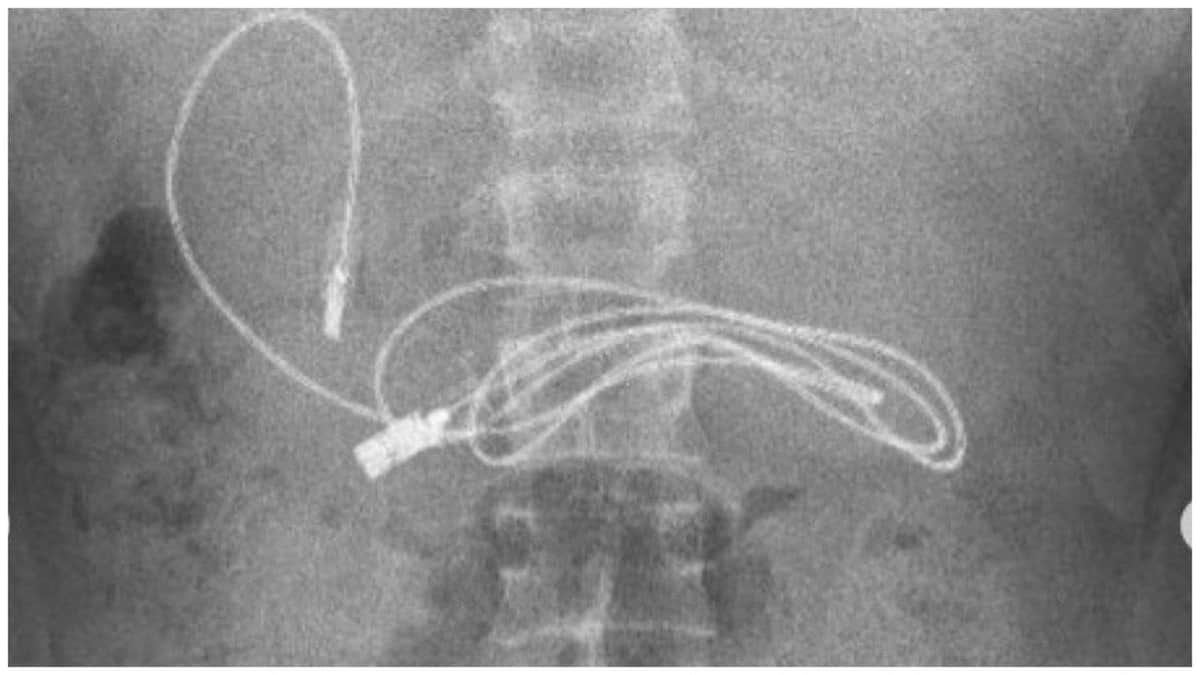

Los doctores informaron que el cable se enredó y llegó hasta su vejiga.

Xu Liyan, doctora del Departamento de Urología, explicó que el cable en el pene del chico se había retorcido y enredado complicando las cosas.

Sin embargo, el nudo era tan grande que no pasaba por la uretra y esto podría generarle lesiones al chico.

Después, decidieron hacer una incisión en el punto donde el cable estaba anudado, antes de quitarlo.